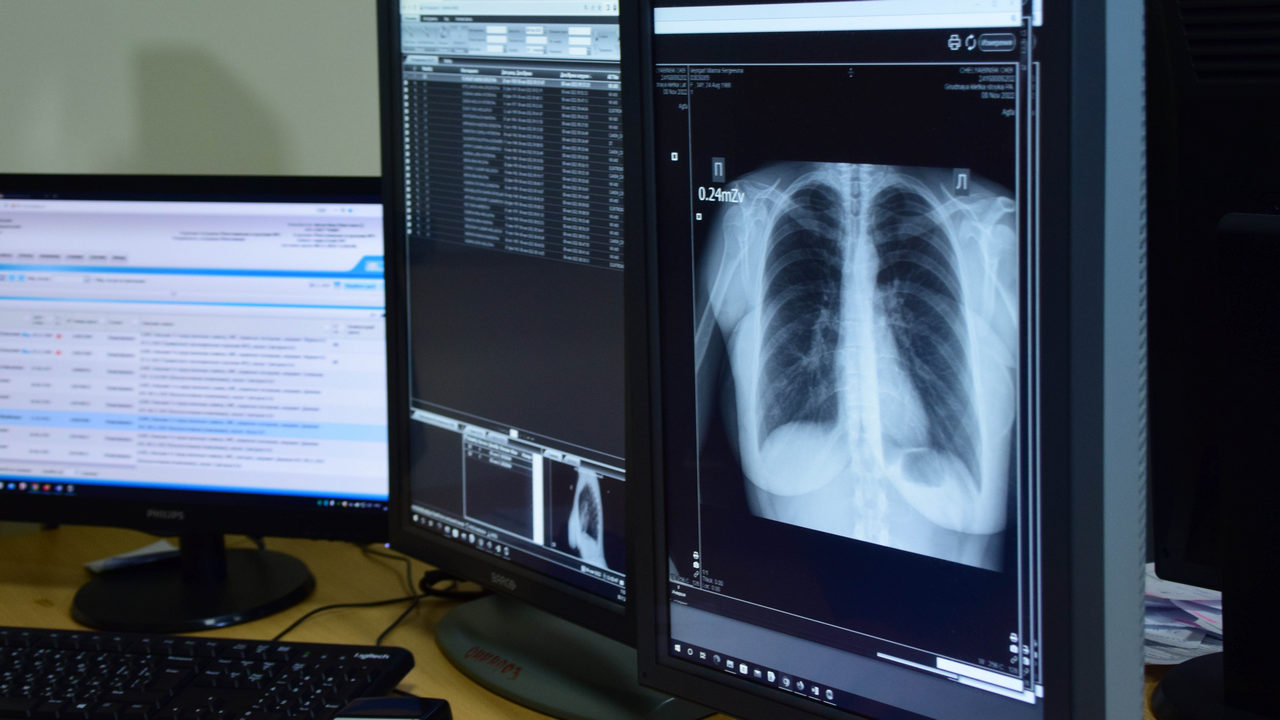

На Кировке будет развернут передвижной медицинский кабинет. Врачи областного противотуберкулезного диспансера ждут южноуральцев, которые хотели бы пройти флюорографическое исследование. Для этого при себе необходимо иметь паспорт. А сотрудники областного центра СПИД проведут бесплатное и анонимное тестирование на ВИЧ.